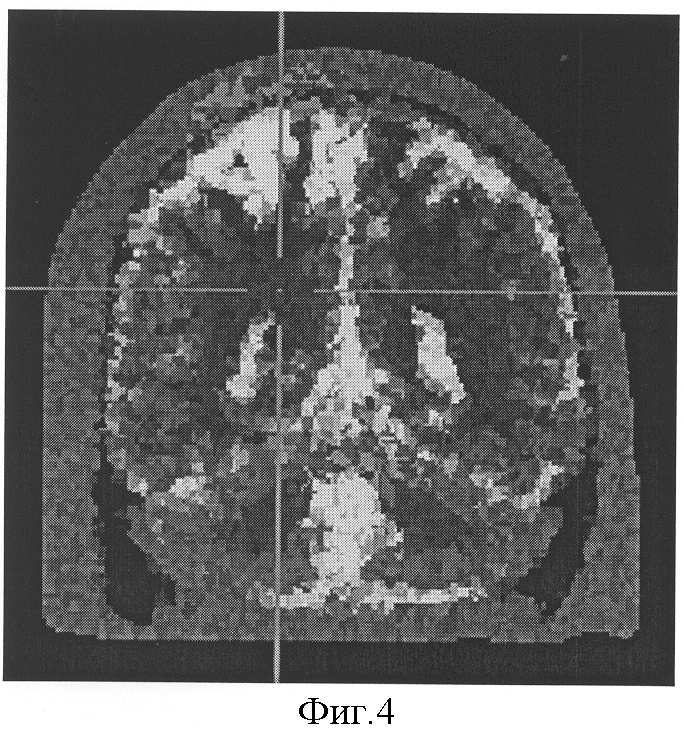

На фиг.4 изображен очаг нарушения перфузии головного мозга по данным электроэмпедансной томографии в правой теменной доли.

Диагноз был подтвержден ангиографически и эхоскопически. При проведение гипоксической пробы была выявлена зона усиленной гидратации (сниженной проводимости ткани) на основании данных электроимпедансной томографии, в правой теменной доли. Фиг.4.